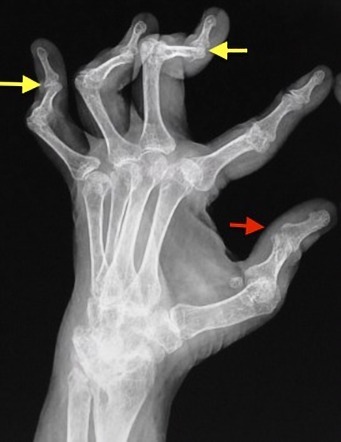

34M with forefoot pain

Psoriatic Arthritis

erosions in the metatarsophalangeal (MTP) and interphalangeal (IP) joints is nonspecific.

However, the florid periostitis strongly suggests either psoriatic arthritis or chronic reactive arthritis.

pencil in cup deformity

Almost always accompanies skin disease, especially nail changes

Mostly involves DIP joints of hands > feet